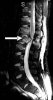

MRI : 척수 원추 증후군(Conus medullaris syndrome)

척추 원추 증후군은 대부분 제11흉추와 제2요추 사이 부위의 손상에 의하여 발생하는데 압박골절이 가장 빈발하는 곳이기도 합니다. 증상은 비반사성 방광(areflexic bladder)을 특징으로 하며, 회음부의 이완성 마비가 발생하면 모든 방광 및 항문주위 근력이 소실되어 대소변이 그냥 흘러 나오게 됩니다. 척수의 신경기능 소실로 구해면체 반사 및 항문 주위 반사(perianal wink)가 나타나지 않는데, 이것은 직접 검사해 보아야 할 수 있습니다.